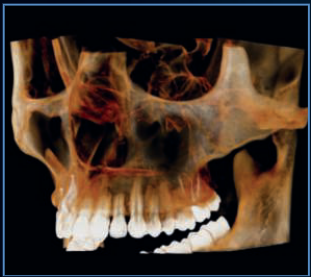

Our flagship high resolution tomograph delivers cutting-edge image quality that allows you to visualize anatomy and pathology beyond traditional CBCT standards. This comes from its unique flat panel detector (FPD), which provides an industry-smallest, 0.2mm focal spot. Investing in the Excelsior ENDO mean offering patients superior diagnostics and setting a practice apart as a leader in dental imaging.

The powerful system components of the PreXion Excelsior Endo enable an extraordinary combination of the most precise 3D imaging, large image detail, lowest radiation exposure, reliable diagnostics and digital planning, which is optimized specifically for endodontic diagnostics and treatment with its flat panel detector (FPD) providing an industry-leading 02.mm focal spot. Its patient management system is designed for secure and networked communication of patient data across multiple rooms within a practice and can be integrated into the existing infrastructure with ease.

PreXion Excelsior ENDO has outstanding resolution with Isotropic Voxel size as low as 48um.